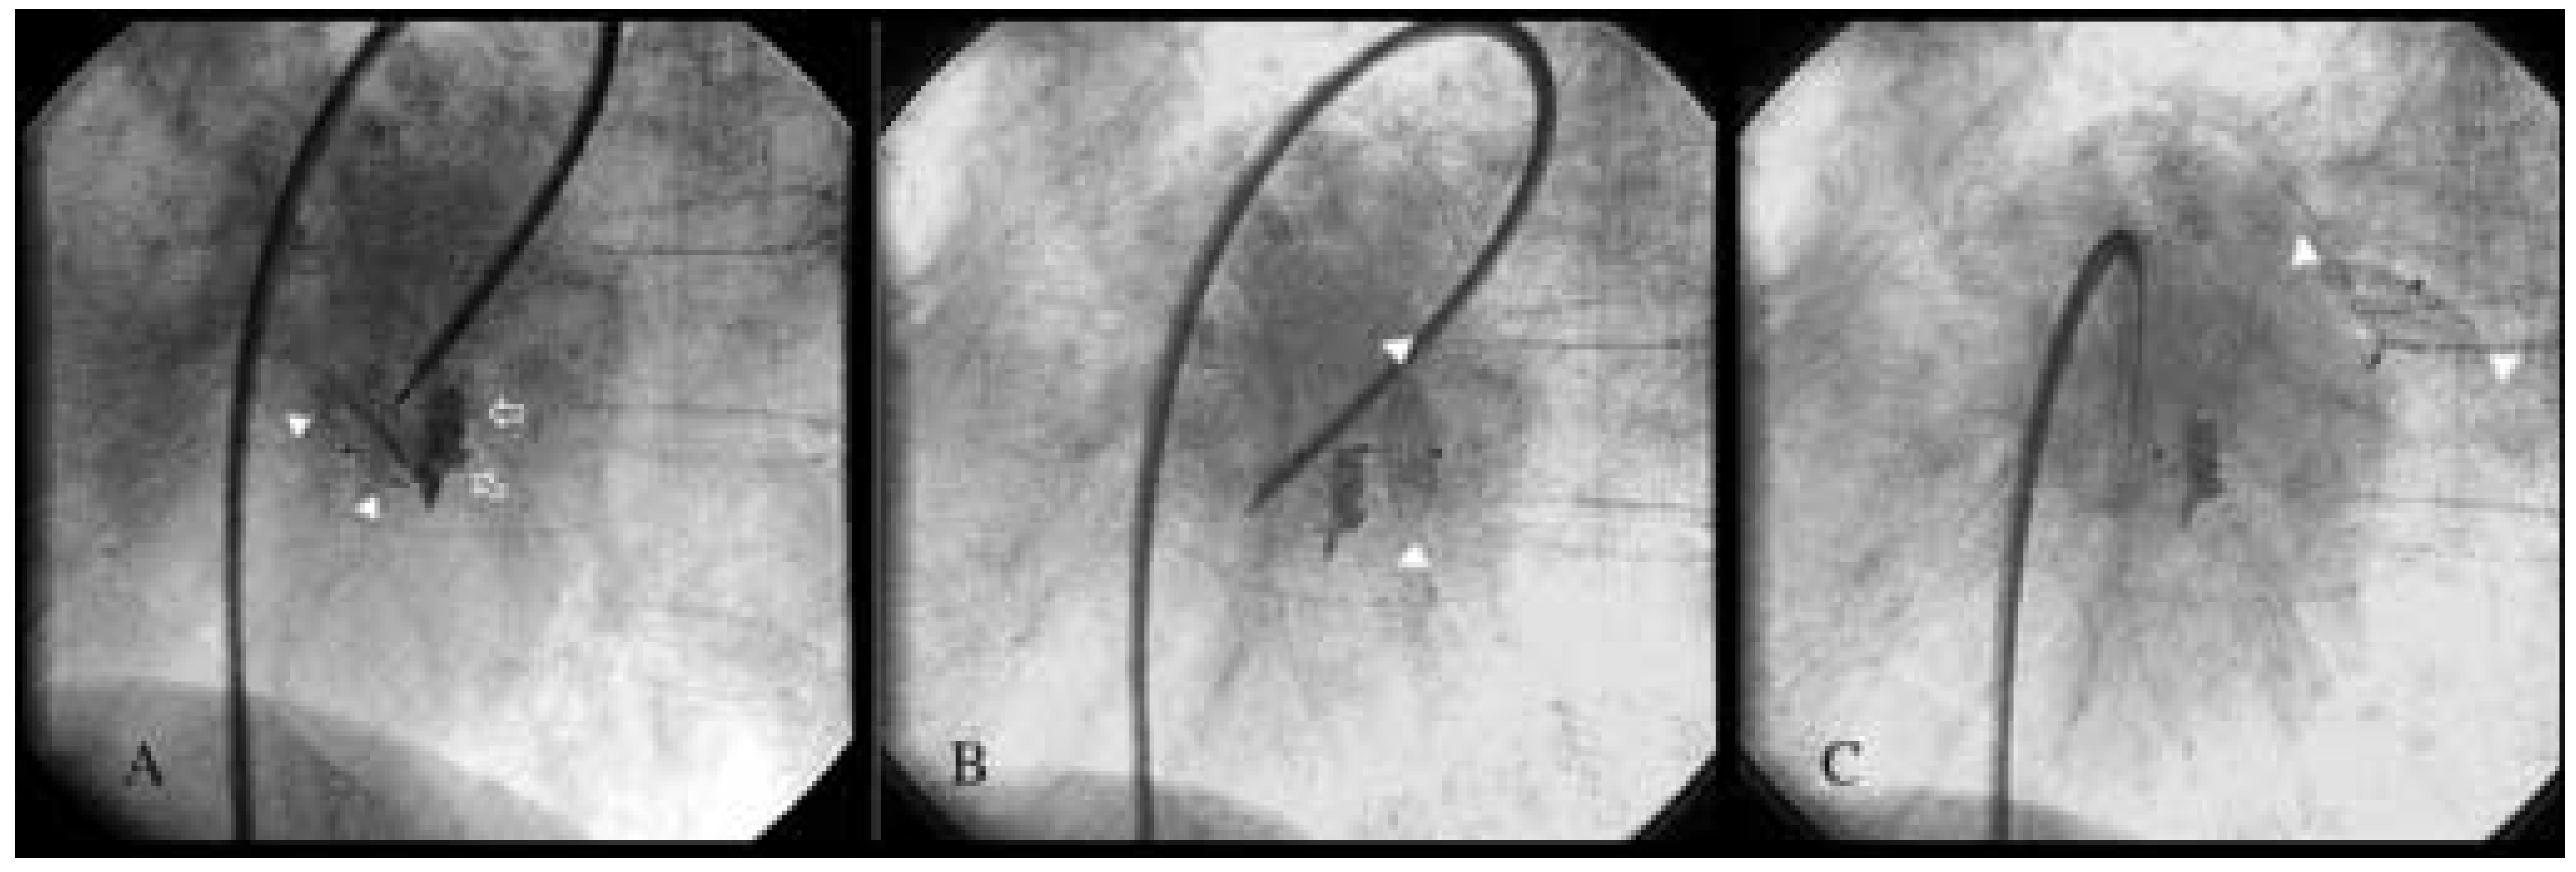

An 80-year-old woman with symptomatic rheumatic mitral valve disease and chronic atrial fibrillation was admitted for mitral valvuloplasty and interventional occlusion of the left atrial appendage. Mitral commissurotomy had been performed 30 years earlier. Because of unstable INR with warfarin therapy, she was at increased risk for bleeding and thromboembolism. The left atrium was grotesquely dilated (10.3 × 4.6 cm) and showed spontaneous echo contrast. Severe calcification of the mitral valve and mitral annulus resulted in significant stenosis (mitral valve area 1.0 cm2, mean pressure gradient 11 mm Hg) and mild mitral regurgitation. The coronary arteries were normal and mitral valvuloplasty was performed resulting in only moderate improvement with a valve area of 1.3 cm2. After fluoroscopic identification of the atypically located left atrial appendage by contrast medium injection, a 10 mm Amplatzer septal occluder was inserted (fig. 1A). However, after its detachment from the catheter, the device dislodged from the left atrial appendage and was found floating in the left atrium (fig. 1B, C). In light of the residual mitral stenosis with moderate regurgitation, no attempt was made to retrieve the dislodged device percutaneously. The patient was left with bed rest and heparin. The next day the device was still in the left atrium (fig. 2) and mitral valve replacement was performed. The occluder was removed from the left atrium and found clean from thrombosis (fig. 3). An atrial septal tear resulting from the transseptal puncture was repaired, and the left atrial appendage was obliterated. Postoperative recovery was uneventful.

Figure 1. A. Atypically located left atrial appendage outlined with contrast medium (arrows) with the 10 mm Amplatzer septal occluder inserted (arrowheads). B, C. Occluder (arrowheads) dislodges into left atrium after detachment from the catheter.